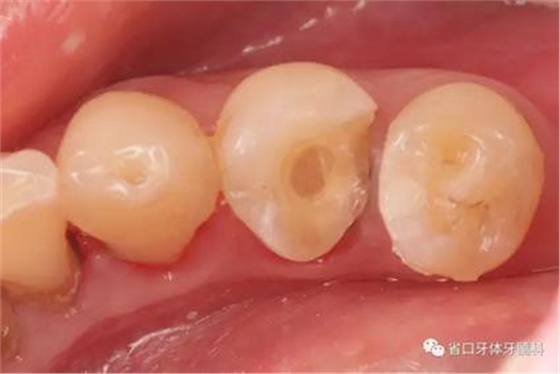

檢查:34遠(yuǎn)中鄰合面可見白色暫封物,叩痛±,不松,牙齦略紅腫。35近中鄰面齲壞,及牙本質(zhì)中層,叩痛-,冷測(cè)同對(duì)照,不松,牙齦未見異常。36、37缺失。

診斷:34慢性牙髓炎;35MO中齲

圖4:牙體預(yù)備術(shù)前照

圖5:顯微鏡下34牙體預(yù)備,拋光,35近中樹脂直接充填,選色偏白